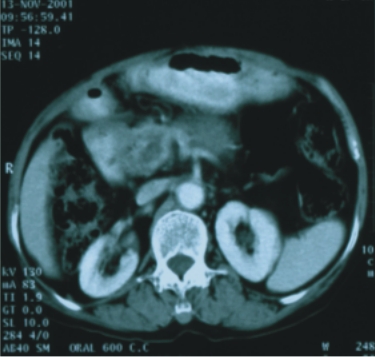

56歲/男性 (肝癌合併後腹腔淋巴腺轉移) |

74歲/男性 (直腸癌合併後腹腔淋巴腺轉移) |

||

| 90/5/2

(治療前) |

90/6/30(治療後) |

90/8/16(治療前) |

90/12/21(治療後) |